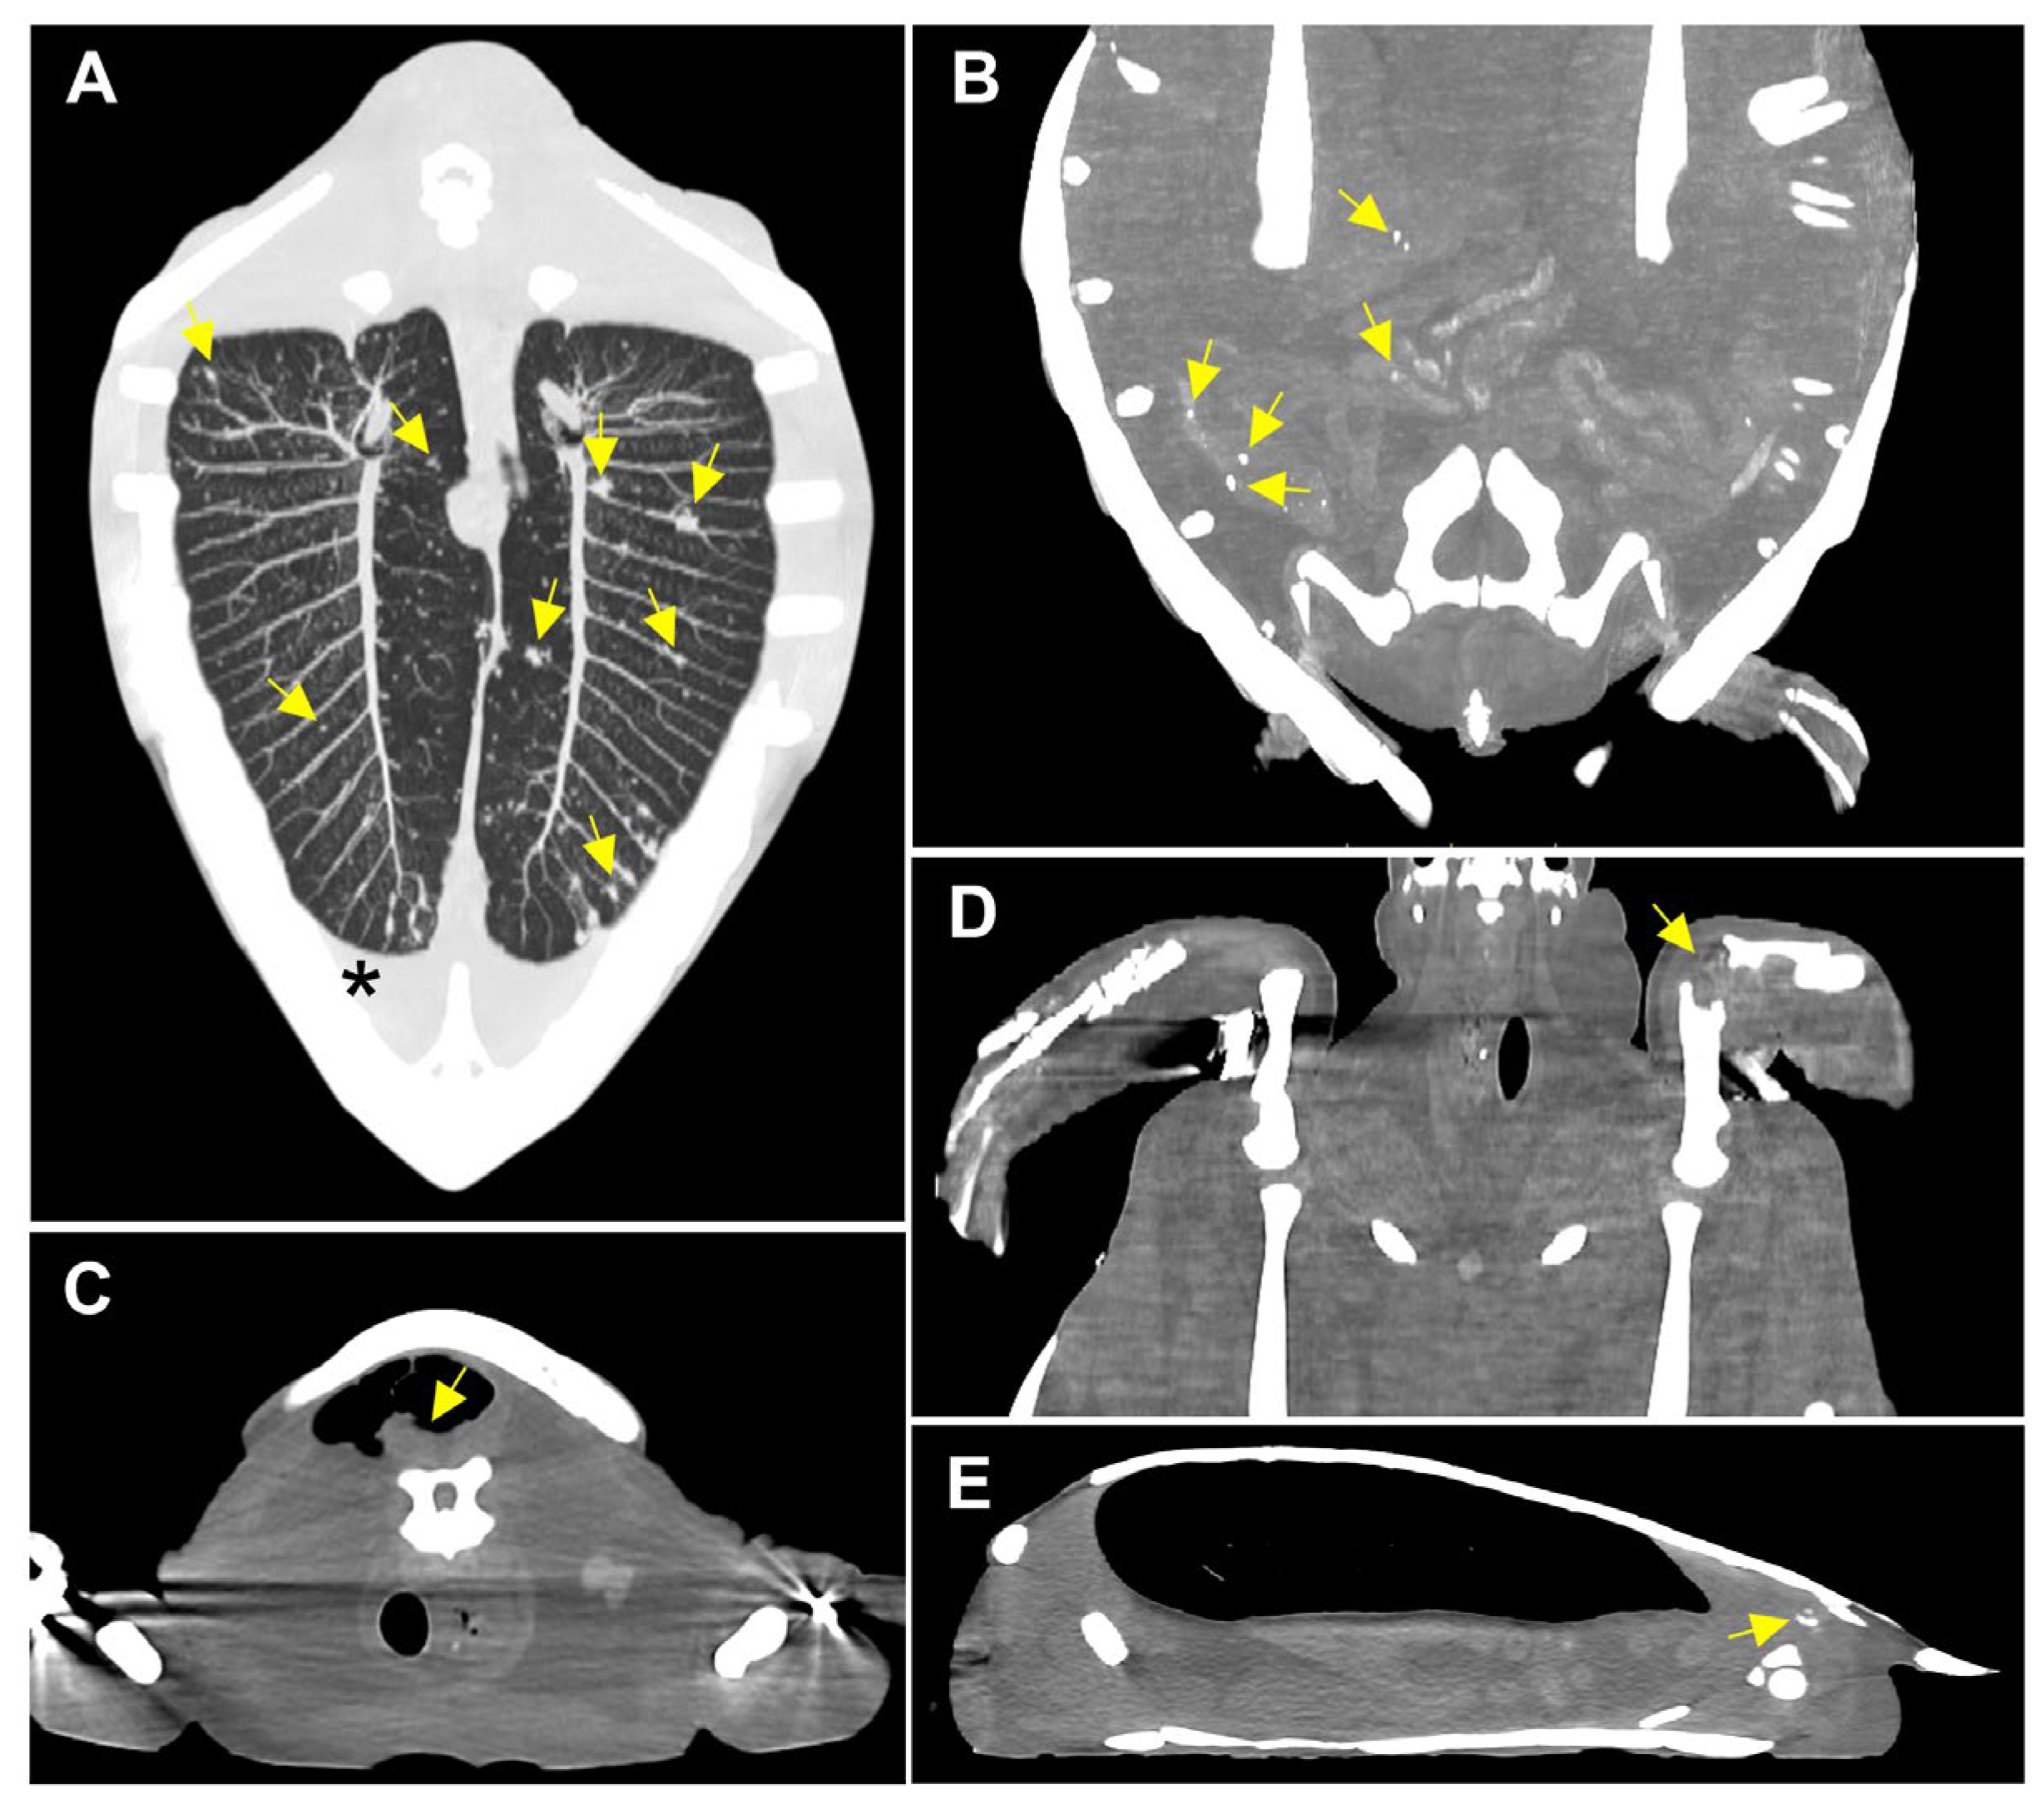

3.1.2. Radiological Findings

3.2. Postmortem Examination